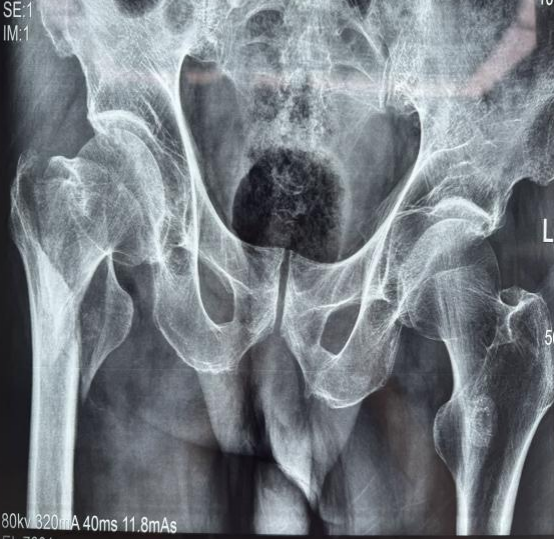

患者,男性,86歲,因不慎摔倒致右髖部疼痛、活動受限數(shù)小時入院。查體示右下肢外旋畸形,右髖部壓痛明顯,活動受限。X線片診斷為右側(cè)股骨轉(zhuǎn)子間骨折?;颊呒韧邪滩〔∈罚灰?guī)律服藥。經(jīng)多學(xué)科術(shù)前討論,綜合評估患者身體狀況后,決定行人工股骨頭置換術(shù)以迅速恢復(fù)髖關(guān)節(jié)功能,減少臥床時間,降低并發(fā)癥風(fēng)險?;颊咝g(shù)后第2天助步器輔助下逐步下床活動。

術(shù)前與術(shù)后影像學(xué)對比